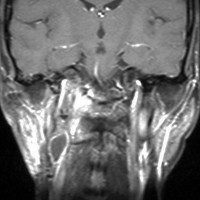

遺伝歴があり30代くらいです。黄色の矢印で示す右側はglomus vagale,左側は上がglomus jugulare、左下がglomus caroticumです。教科書に載せたいくらい典型的な部位に発生しています。無症状ですからもちろん治療はしません。6年くらい経過観察していますがほとんど増大もしません。